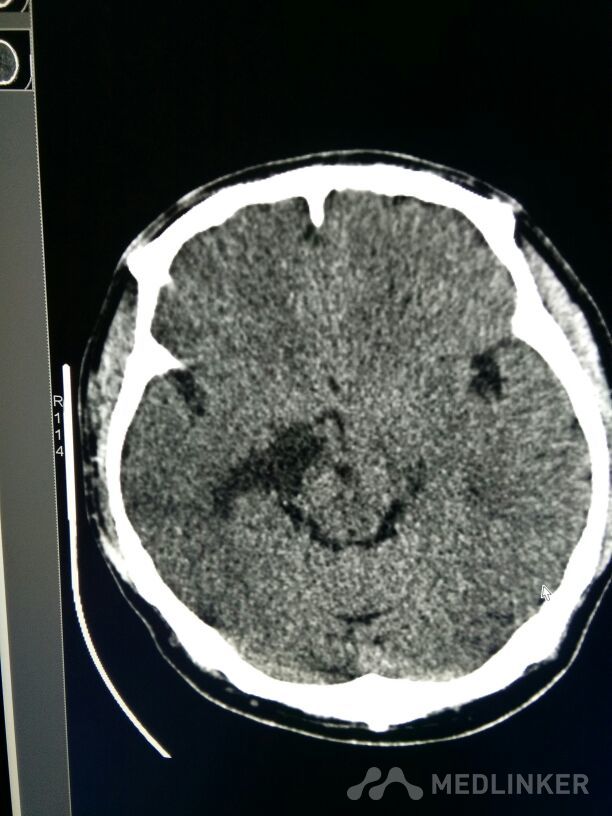

考虑表皮样囊肿?

表皮样囊肿